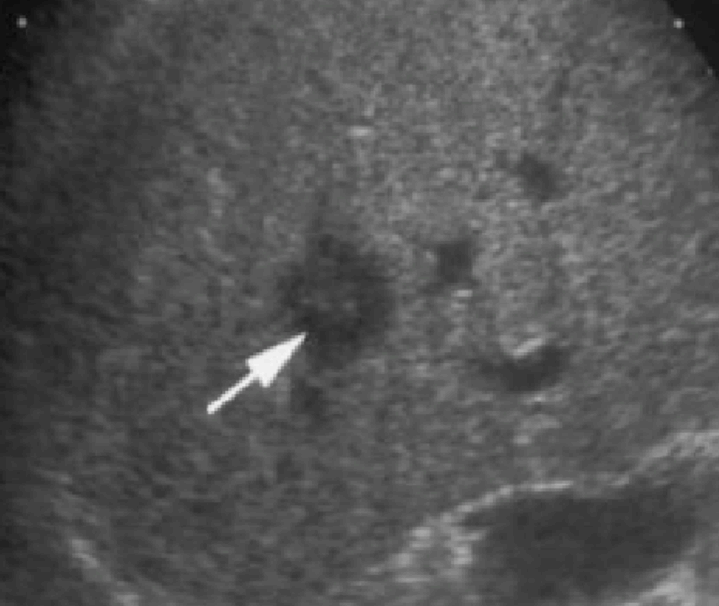

2~3cm hcc sono features ③ 3~5 cm hcc sono finding

- hypo-hyperechoic

- heterogenous

- irregular

- hump sign (표면에 존재하는 결절형 종괴에서 간표면으로 종괴가 돌출하는 경우 나타난다)

- mosaic pattern (종양내부에 괴사나 출혈이 생겨 내부에 균열이 있는 것처럼 보이는 모자이크패턴이 나타남)

- color doppler : internal mass pattern (feeding artery)